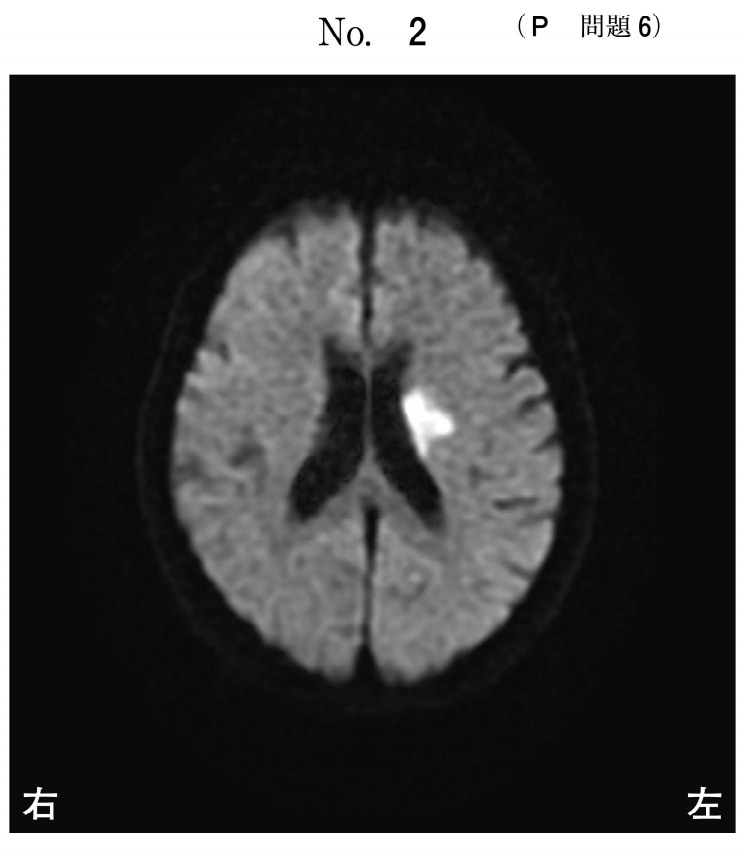

75歳の女性。右利き。脳梗塞を発症し救急車で搬入された。発症翌日に症状の悪化を認めた。発症3日目の頭部MRIの拡散強調像(別冊No.2)を別に示す。

最も出現しやすい症状はどれか。